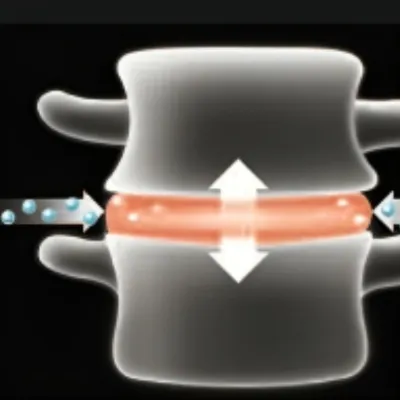

Our Advanced Laser-Enhanced Spinal Decompression™ Therapy is designed to gently stretch the spine, creating negative pressure within the discs. This process encourages the retraction of bulging or herniated discs and promotes the influx of healing nutrients, reducing inflammation and pain. Our unique methods relieve tension and pressure on the spinal discs, moving the affected parts of the spine back to their natural position. Additionally, the increased blood flow introduces more nutrients to the discs, promoting healing from within and significantly improving patient outcomes.

1) Creates space between vertebrae

2) Allows disc to regain volume

3) Allows disc absorption of gelatinous core

4) Reduces pressure on nerves